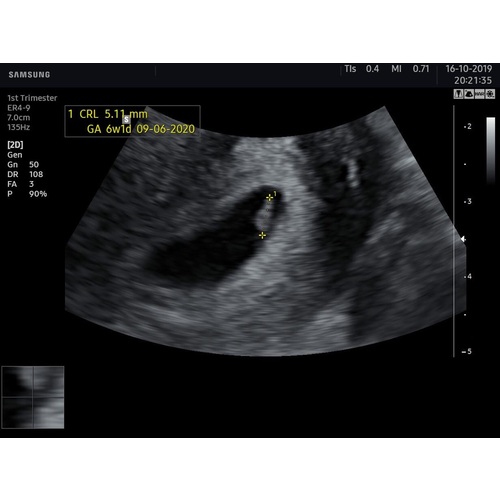

Ik had met 6+4 een echo. Hartje klopte nét. Je ziet een streepje. Meer niet. 🙈

Ik had met 6+4 een echo. Hartje klopte nét. Je ziet een streepje. Meer niet ...

Dit was afgelopen zomer. Ik was net geen 6w zwanger, klopte een hartje. Ik ...

Dit was de allereerste echo

Dankje! Deze was met 5+5, nu ik ze zo even bij heb gepakt zie ik dat ik meer heb gehad dan ik dacht 🙈 ( dit ivm eerdere missed abortion ) ook nog met 6+4, 9+3 en toen de 12 weken echo. Zelf met 15 weken geslachts bepalende echo laten maken en toevallig vandaag de 20 weken echo gehad. 🎀💗